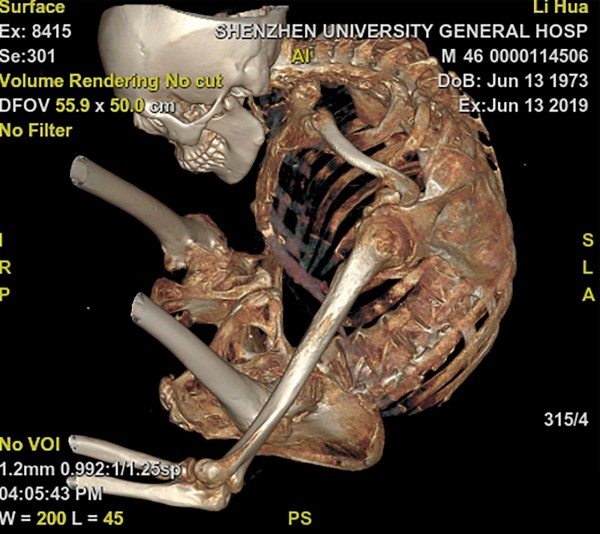

Μέσα από μια σειρά τεσσάρων διαδοχικών επεμβάσεων οι γιατροί στο Γενικό Πανεπιστημιακό Νοσοκομείο της πόλης Σενζέν «ανακατασκεύασαν» ολόκληρη τη σπονδυλική στήλη του 46χρονου Li Hua.

Ο Li είχε διαγνωσθεί με αγκυλοποιητική σπονδυλοαρθρίτιδα το 1991 σε νεαρή ηλικία 18 ετών. Από την διάγνωση του και μετά ο ιδιος «δίπλωνε» ολοένα και περισσότερο με το πέρασμα του χρόνου. Η οικογενεια του δεν είχε την οικονομική δυνατότητα για να του προσφέρουν την κατάλληλη ιατρική περίθαλψη.

Ο γιατρός είπε: “Σε ένα πιο σύνηθες περιστατικό ένας ασθενής θα μπορούσε τουλάχιστον να ανυψώσει το κεφάλι του, αλλά ο Λι δεν μπορούσε να κάνει ούτε αυτό. Υπήρχε ένα κενό μόλις 5 εκατοστών ανάμεσα στο πηγούνι και στους μηρούς του. Η μόνη μας επιλογή ήταν να σπάσουμε τα οστά του ένα προς ένα: μηρός, αυχενικοί σπόνδυλοι, θωρακικοί σπόνδυλοι, οσφυϊκοί σπόνδυλοι και στη συνέχεια να ισιώσουμε ολόκληρη τη σπονδυλική του στήλη. Οι κίνδυνοι ήταν 20 έως 30 φορές μεγαλύτεροι από τις συνήθεις περιπτώσεις χειρουργικής επέμβασης στη σπονδυλική στήλη και οι πιθανότητες να γίνει παραπληγικός ήταν επίσης πολύ υψηλές”.

Οι μετεγχειρητικές εικόνες που δόθηκαν στη δημοσιότητα από το νοσοκομείο δείχνουν ότι ολόκληρο το σώμα του Li έχει πλέον ξεδιπλώσει.